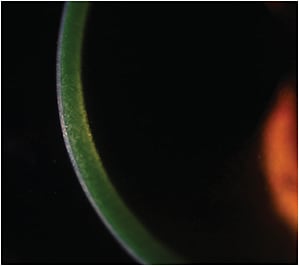

The “epi-off” method of collagen corneal cross-linking is illustrated here.

Slit-lamp photo of riboflavin loading during epi-on CXL shows good saturation.